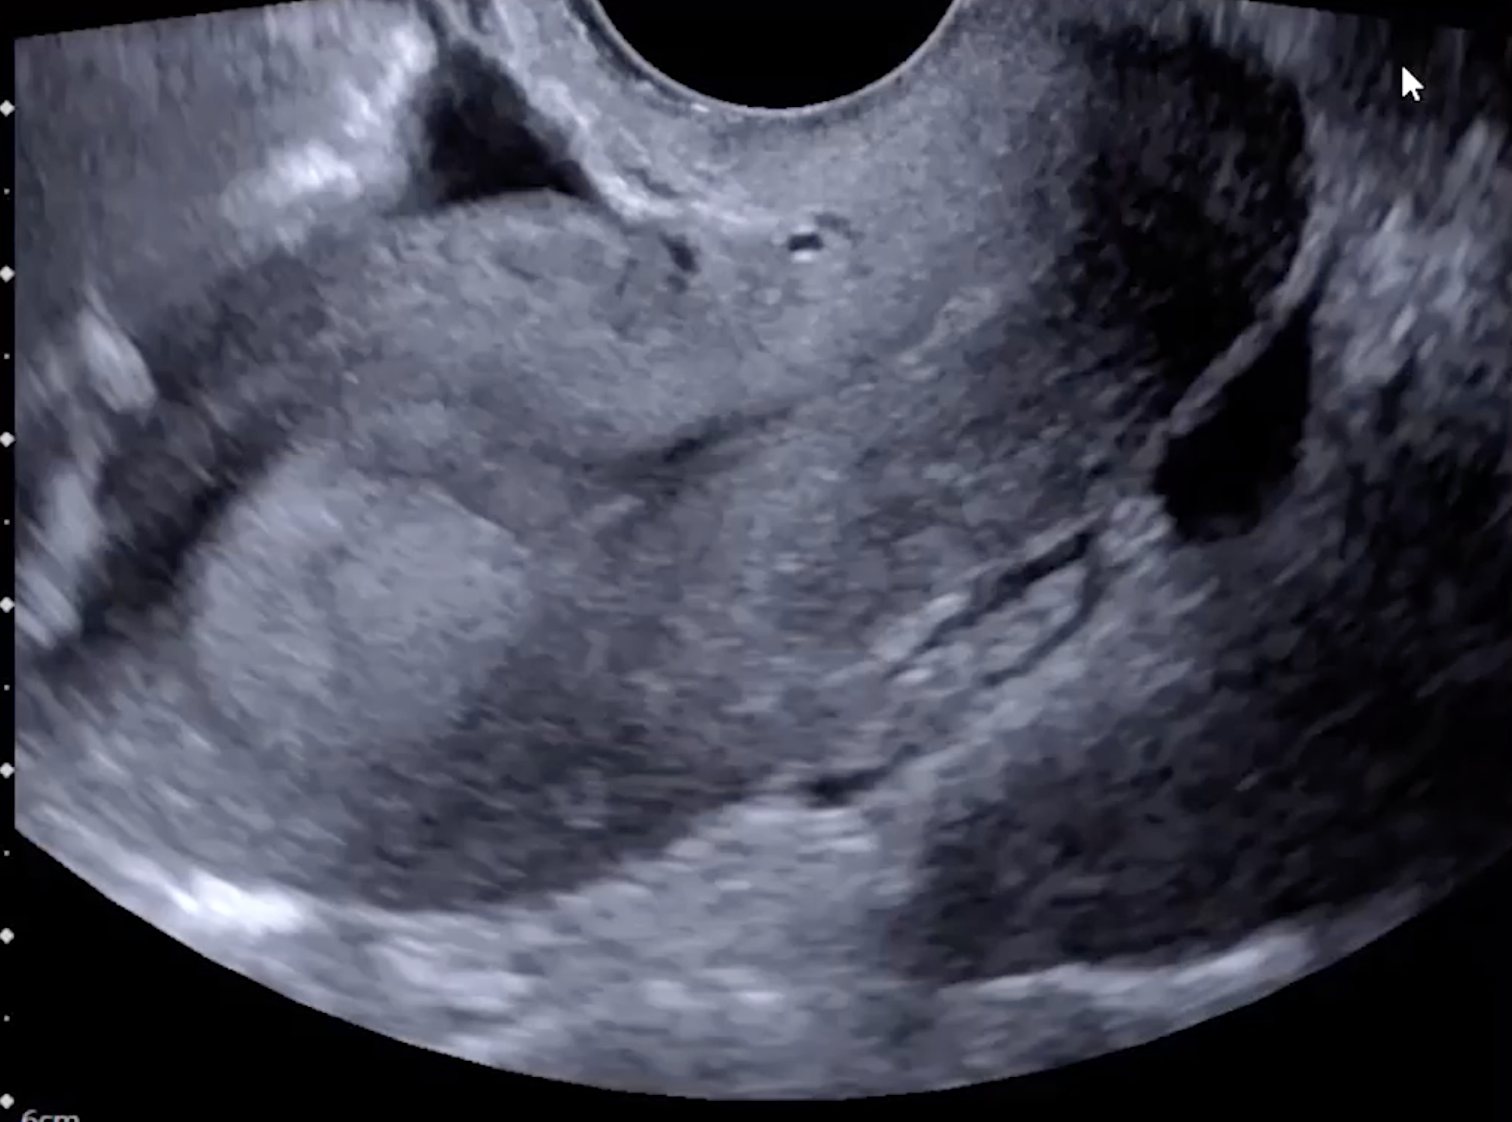

• Imaging findings

• Enlarged ovary (>4 cm)

• Lack of doppler flow (not required, can have torsion with flow!)

• Peripheralization of ovarian follicles (also seen in PCOS)

• Free pelvic fluid

Peripheralization of follicles and no internal doppler flow within the ovary